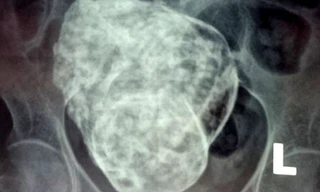

TP - Vôi hóa càng nhiều càng cản trở sự lưu thông của dòng máu và dẫn tới sự xuất hiện các mảng xơ vữa, gây tắc lòng mạch máu. Đây là nguyên nhân dẫn đến tai biến mạch máu não và nhồi máu cơ tim. Sự vôi hóa này hình thành bởi canxi vào cơ thể đã chạy thẳng đến các mạch máu mà không phải là xương.